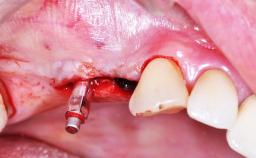

- Details of surgical techniques for SFE